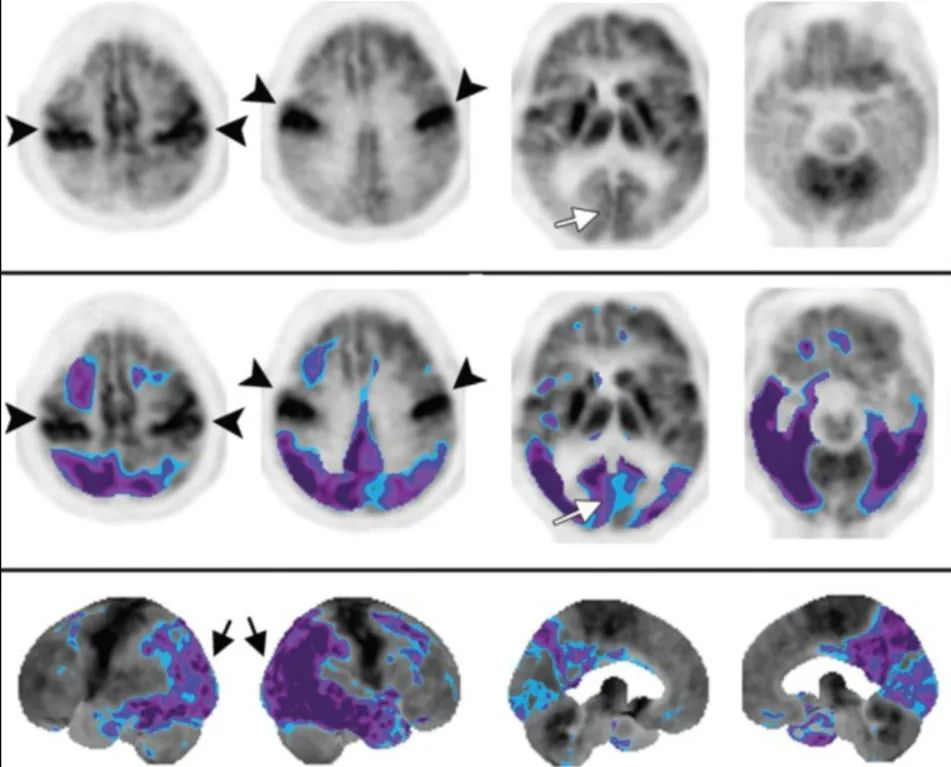

PET 是鉴别 PD 和 APS 的有用工具。保存基底节的代谢活性是 FDG-PET 中 PD 的一个重要特征,而 APS 基底节代谢活性明显减低。

FDG-PET显示PD基底节代谢活动得到保留,而MSA基底节代谢明显减低